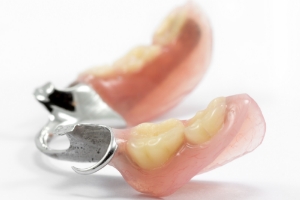

| 施術内容 | 右下奥歯3本欠損。入れ歯を使っていたが金具が折れて数年使っていない。金具のない目立たない入れ歯を希望していたが、固定式で安定したインプラント治療へ。インプラントは2本、冠は3本ブリッジ。 |

|---|---|

| 治療期間 | 4ヶ月 |

| 治療費 | 約68万円(チタンブリッジ) |

| 副作用・リスク | インプラント治療は手術を伴います。腫れや痛みが少なくなるよう努力をしておりますが、多少の腫れや痛みが出ます。しかし、痛み止めで抑えられる程度ですのでご安心ください。 |

※表示は全て税込表示です。